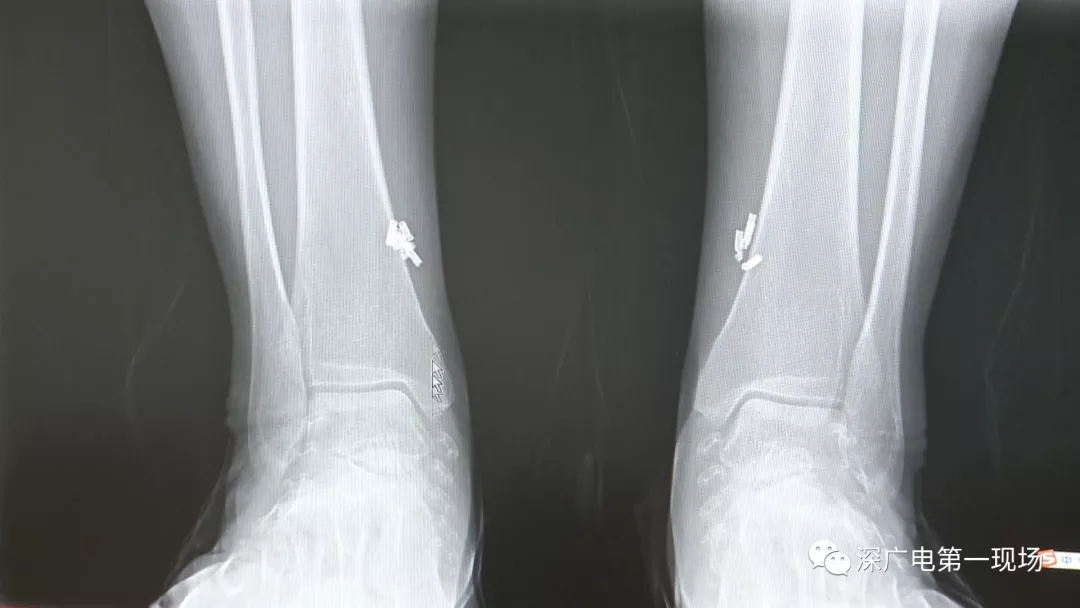

深圳一女子全身被植入彈簧圈,數量多到驚人!竟是為治這病…

出于保護患者,我們沒有直接采訪,但是通過醫(yī)生的介紹,記者了解到,病人是個36歲的女性,2歲開始就有癲癇病史,而且藥物治療也并不見效。

多方打聽之后,在山東某診所用全身埋彈簧圈的方式治療癲癇。陶主任介紹,這樣的方式想要治愈,那幾率也等同于撞大運啊!